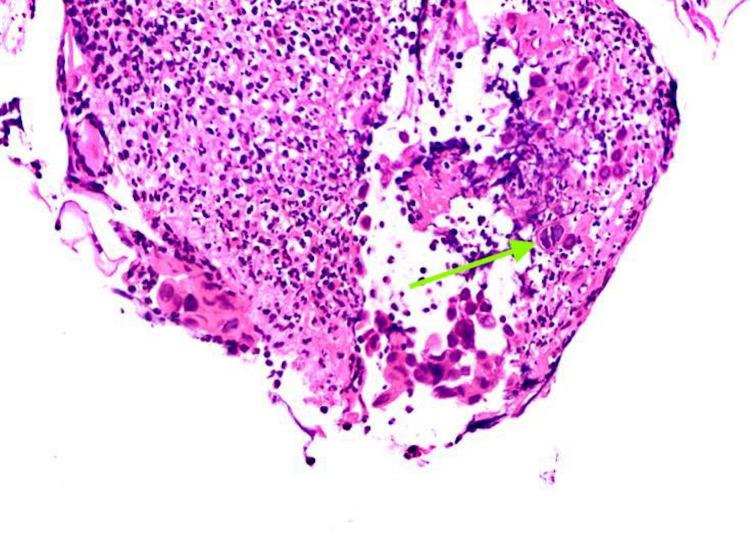

Herpes simplex infection remains the third most common cause of esophagitis following gastric reflux disease and candida infection. This disease usually occurs in immunocompromised individuals; however, it has been frequently reported in healthy individuals. We present a case of a 39-year-old man who presented to the ER with symptoms unusual of herpes esophagitis. He was presumed to be immunocompromised due to uncontrolled diabetes mellitus and chronic alcohol use. Endoscopy revealed features in favor of candidiasis; however, histopathology displayed characteristic features of herpes infection. Herpes esophagitis should thus be suspected in immunocompromised patients with an independent underlying pathology and treated early with antiviral agents like acyclovir to prevent impending complications.

单纯疱疹感染仍是继胃反流病和念珠菌感染之后食管炎的第三大常见病因。这种疾病通常发生在免疫功能低下的个体中;然而,在健康个体中也经常有病例报道。我们报告一例39岁男性患者,他因出现单纯疱疹性食管炎不常见的症状而就诊于急诊室。由于糖尿病控制不佳和长期酗酒,推测他免疫功能低下。内镜检查显示有念珠菌病的特征;然而,组织病理学表现出疱疹感染的特征性表现。因此,对于有独立基础疾病的免疫功能低下患者,应怀疑患有单纯疱疹性食管炎,并应尽早使用阿昔洛韦等抗病毒药物进行治疗,以预防即将出现的并发症。